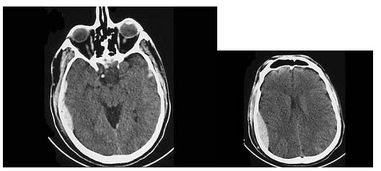

其基本原理是:將人體置于特殊的磁場,用無線電射頻脈沖激發(fā)人體內(nèi)氫原子核,引起氫原子核共振,并吸收能量。在停止射頻脈沖后,氫原子核按特定頻率發(fā)出射電信號(hào),并將吸收的能量釋放出來,被體外的接受器收錄,經(jīng)電子計(jì)算機(jī)處理獲得圖像,這就叫做核磁共振成像。

核磁共振成像技術(shù)是核磁共振在醫(yī)學(xué)領(lǐng)域的應(yīng)用。人體內(nèi)含有非常豐富的水,不同的組織,水的含量也各不相同,如果能夠探測到這些水的分布信息,就能夠繪制出一幅比較完整的人體內(nèi)部結(jié)構(gòu)圖像。

核磁共振成像技術(shù)就是通過識(shí)別水分子中氫原子信號(hào)的分布來推測水分子在人體內(nèi)的分布,進(jìn)而探測人體內(nèi)部結(jié)構(gòu)的技術(shù)。在MRI檢查時(shí),病人要免帶鐵器等磁性物品,如手表、金屬項(xiàng)鏈、假牙、金屬鈕扣、金屬避孕環(huán)等,以免影響磁場的均勻性,造成圖像偽影,不利病灶顯示。